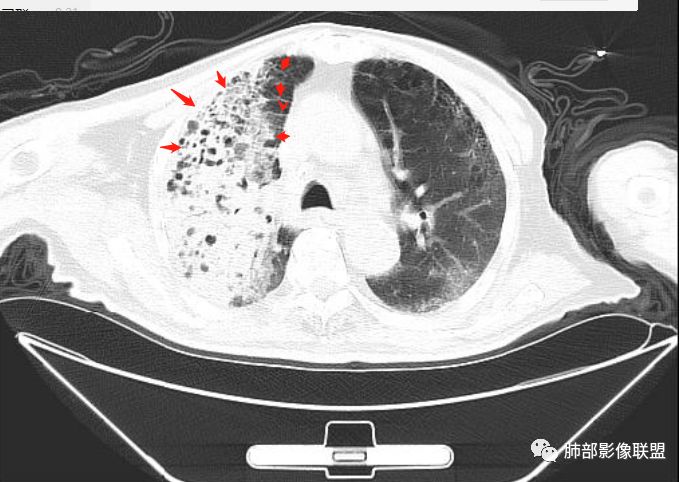

支气管、内部的小囊腔,部分无壁小空洞,病灶部分边界偏清,支持结核

双胞胎的结核与粘液腺癌

粘液腺癌和干酪性肺炎鉴别:

1、结核干酪空洞常很干净,很彻底,而粘液腺癌空洞内有液性成份,不干净。

2、支气管:干酪样肺炎内的支气管破坏的,扩张的,粘液腺癌小支气管多狭窄的堵塞的,大支气管较完好,枯枝征。

3、增强扫描很重要,增强后,结核的坏死很彻底,很少异常强化,(鳞癌也类同)。而粘液腺癌血管常显影,有时是毛糙的,整体密度偏低,哟其实纵膈窗。

4、症状,粘液腺癌白痰为主。

5、这样的结核灶,其实痰检出抗酸杆菌阳性的几率常较大。

6、结核灶周围磨玻璃少见,粘液腺癌磨玻璃影清楚。结核灶常有收缩,钙化,树丫等等。很重要,粘液腺癌分布弥漫,远处飘散的边界清楚的磨玻璃结节影有重要诊断意义。

7、形态,结核收缩,粘液腺癌局部膨胀,叶间裂有时候是膨胀下坠的。

粘液腺癌的很少见纵隔淋巴结肿大,而其他腺癌常见。

如果胸膜下有间隙,不支持肺炎型肺癌